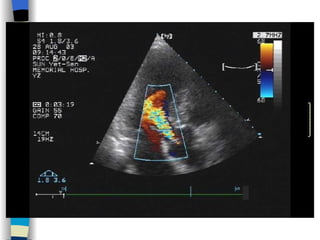

Echocardiography 1 、 Display anatomy of the mitral valve apparatus Useful in determining the etiology of MR ( 2D ) 2 、 Confirm the existence of MR Doppler   (color, spectrum): reveal high-velocity jet into LA during systole Sensitivity~100% Estimate the severity of MR < 4 cm2  Mild ( Color flow jet area )  4~8 cm2  Moderate  > 8 cm2  Severe 3 、 Measure cardiac chamber sizes, evaluate LV function, pulmonary artery pressure, provide data concerning other valvular lesions

Echocardiography 1 、Display anatomy of the mitral valve apparatus Useful in determining the etiology of MR ( 2D ) 2 、 Confirm the existence of MR Doppler (color, spectrum): reveal high-velocity jet into LA during systole Sensitivity~100% Estimate the severity of MR < 4 cm2 Mild ( Color flow jet area ) 4~8 cm2 Moderate > 8 cm2 Severe 3 、 Measure cardiac chamber sizes, evaluate LV function, pulmonary artery pressure, provide data concerning other valvular lesions